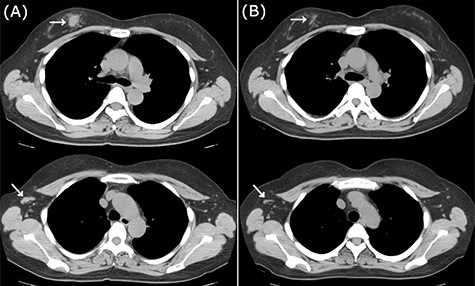

CT images of left breast tumor before and after treatment. (A) Chest CT displaying a nodule in the left breast (top, arrowhead) and lymph node swelling in the left axilla (bottom, arrowhead); (B) Tumors in both the left breast (top, arrowhead, arrowhead) and the axillary lymph node (bottom, arrowhead, arrowhead) shrank after carboplatin and paclitaxel administration.

Because of the early onset of the opposite breast, we administered a combination of carboplatin (area under the concentration-time curve (AUC) 6.0) and paclitaxel (100 mg/m2) every 3 weeks for seven courses. Radiological analysis showed a favorable response (Fig. 5B), and she subsequently underwent breast-conserving surgery with axillary LN dissection. Pathological analysis demonstrated a pCR in the left breast and axillary LNs. She then underwent adjuvant radiotherapy in her left breast. There have been no signs of recurrence 2 years after the treatment.